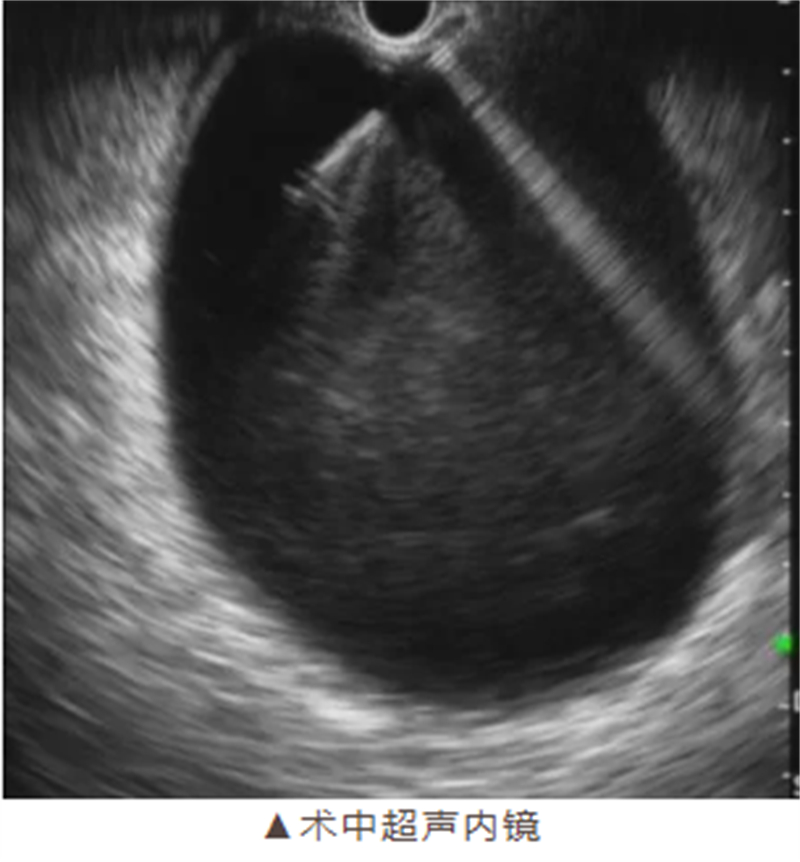

手術(shù)如期進(jìn)行,在麻醉科團(tuán)隊(duì)的密切配合下,消化病肝膽胰疾病診療中心手術(shù)團(tuán)隊(duì)嫻熟地操作超聲內(nèi)鏡,準(zhǔn)確定位囊腫位置,避開重要血管和器官,成功完成穿刺引流并植入支架。整個(gè)手術(shù)過程僅耗時(shí)約40分鐘,術(shù)中無出血,展現(xiàn)了柳州市人民醫(yī)院醫(yī)療團(tuán)隊(duì)高超的技術(shù)水平和專業(yè)素養(yǎng)。

超聲內(nèi)鏡引導(dǎo)下的穿刺引流術(shù)則具有獨(dú)特優(yōu)勢。它利用實(shí)時(shí)超聲引導(dǎo),精準(zhǔn)定位囊腫位置,避開重要血管和器官,通過自然腔道入路進(jìn)行穿刺引流,體表無創(chuàng)口,大大降低了手術(shù)風(fēng)險(xiǎn)和患者的痛苦。同時(shí),留置支架還能顯著降低復(fù)發(fā)率,使患者術(shù)后能夠迅速恢復(fù)進(jìn)食和正常生活。